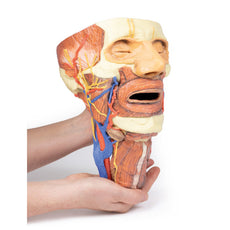

The head and neck of the specimen provides views of both superficial and deep structures in the region. The calotte has been removed ~2cm superior to the orbits to expose the brain in relation to the endocranial cavity. The transverse section through the cerebrum demonstrates the relation of the grey matter cortex to the white matter medulla, as well as the lateral ventricles with a small amount of choroid plexus visible in the base of both spaces. The skin and superficial fascia on the right side has been retained and false-coloured to display the angiosomes of the face and posterior neck. On the left side, the superficial tissues have been dissected to expose the muscles of facial expression, muscles of mastication, and deeper structures of the infratemporal fossa including the lingual nerve, terminal branches of the external carotid artery into the superficial temporal and maxillary arteries.

The carotid sheath has been opened on both sides of the neck, and the internal jugular veins and sternocleidomastoid muscles largely removed, to expose the pathway of the common carotid arteries, internal and external carotid arteries, and the vagus nerves. On the right side, the great auricular nerve ascends towards the face, while the hypoglossal nerve can be seen adjacent to the exposed stylohyoid ligament and supra- and infrahyoid muscles. A large thyroid gland is present bilaterally inferior to the thyroid cartilage, with a well-preserved superior thyroid artery and inferior thyroid vein on the right side and across the midline.

The head and neck of the specimen provides views of both superficial and deep structures in the region. The calotte has been removed ~2cm superior to the orbits to expose the brain in relation to the endocranial cavity. The transverse section through the cerebrum demonstrates the relation of the grey matter cortex to the white matter medulla, as well as the lateral ventricles with a small amount of choroid plexus visible in the base of both spaces. The skin and superficial fascia on the right side has been retained and false-coloured to display the angiosomes of the face and posterior neck. On the left side, the superficial tissues have been dissected to expose the muscles of facial expression, muscles of mastication, and deeper structures of the infratemporal fossa including the lingual nerve, terminal branches of the external carotid artery into the superficial temporal and maxillary arteries.

The carotid sheath has been opened on both sides of the neck, and the internal jugular veins and sternocleidomastoid muscles largely removed, to expose the pathway of the common carotid arteries, internal and external carotid arteries, and the vagus nerves. On the right side, the great auricular nerve ascends towards the face, while the hypoglossal nerve can be seen adjacent to the exposed stylohyoid ligament and supra- and infrahyoid muscles. A large thyroid gland is present bilaterally inferior to the thyroid cartilage, with a well-preserved superior thyroid artery and inferior thyroid vein on the right side and across the midline.